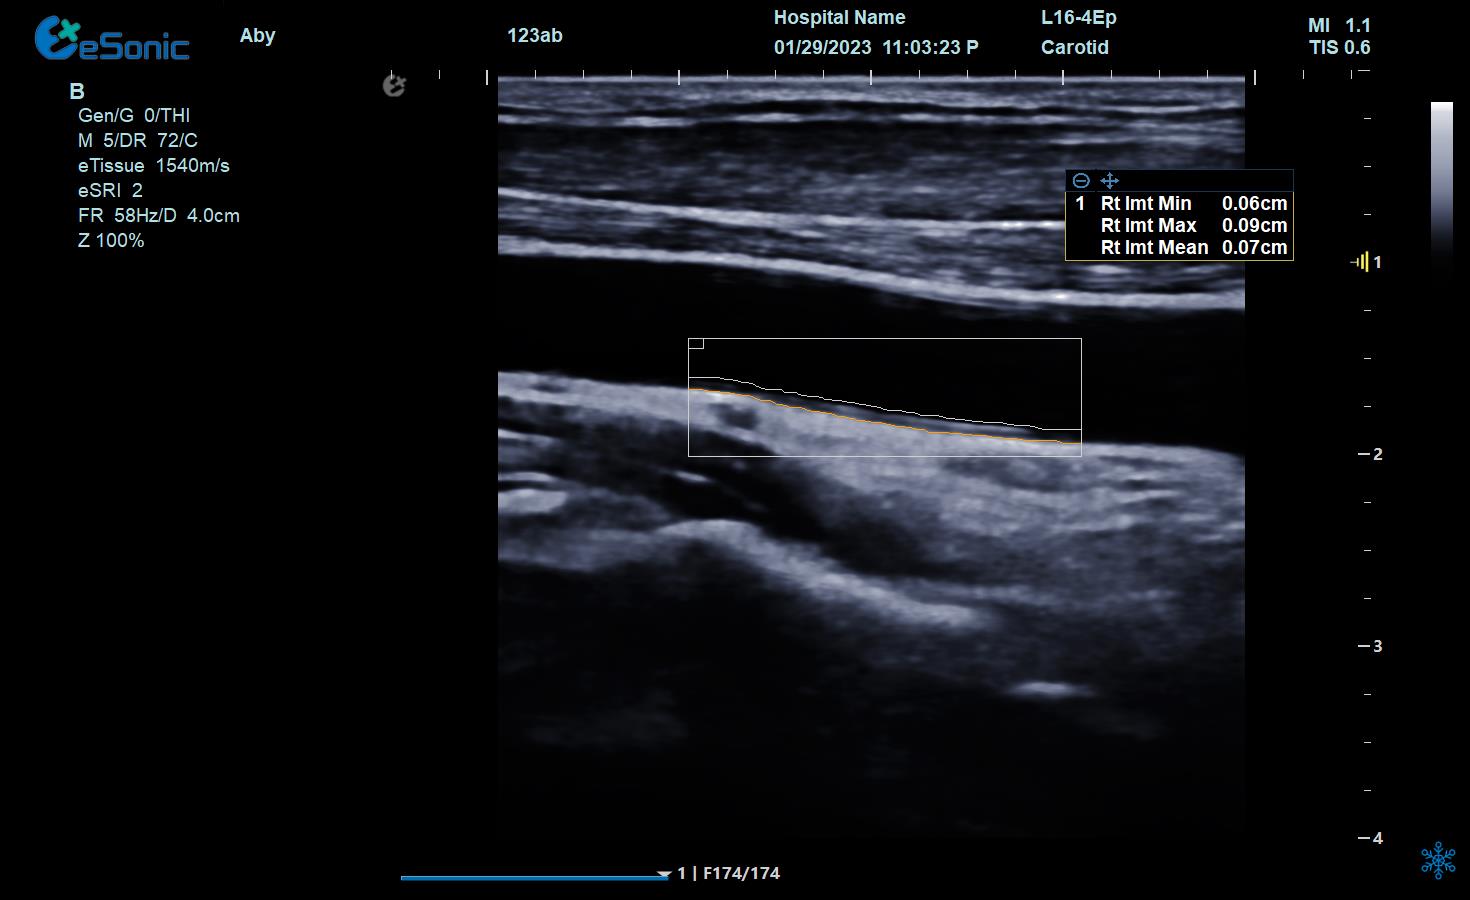

e 智IMT